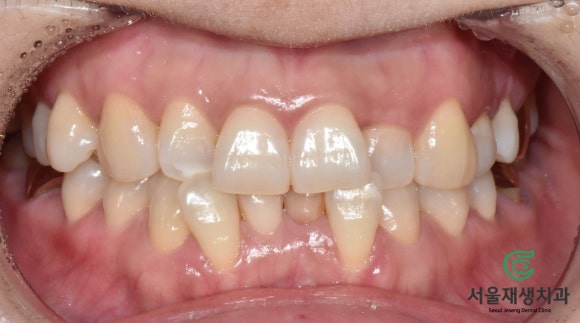

신경치료 후 미백치료(실활치미백)

비포&애프터

![[치아미백] 예전에 부딪힌 앞니가 까맣게 변했어요. 신경이 죽은 치아를 하얗게 돌려놓기! (서울재생치과) 관련 이미지 11](https://pub-9f2bb3498faf4d1d8714b41df24753e3.r2.dev/content/clinics/archive/nqmm0udu86/naver_blog/honeybeevuvu/assets/by_hash/952f5d55b0c723d7c3af55773f211beb621882c01b82c41b40c66d7eb68abf17.jpg)

치료 전 사진과 비교하니

한층 더 드라마틱하지요?^^

서울재생치과 준원장의 권유로

긴가민가한 상태로 시작하셨는데,

만족스러운 결과를 얻으셔서

매우 기뻐하셨습니다^^